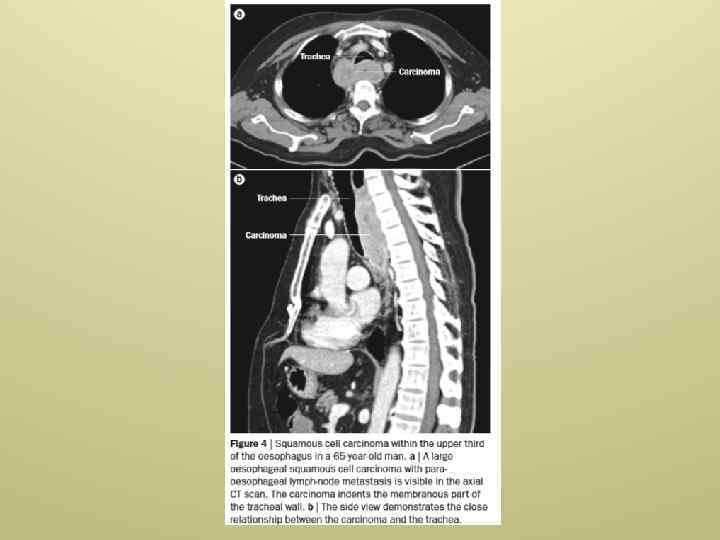

Диагностика